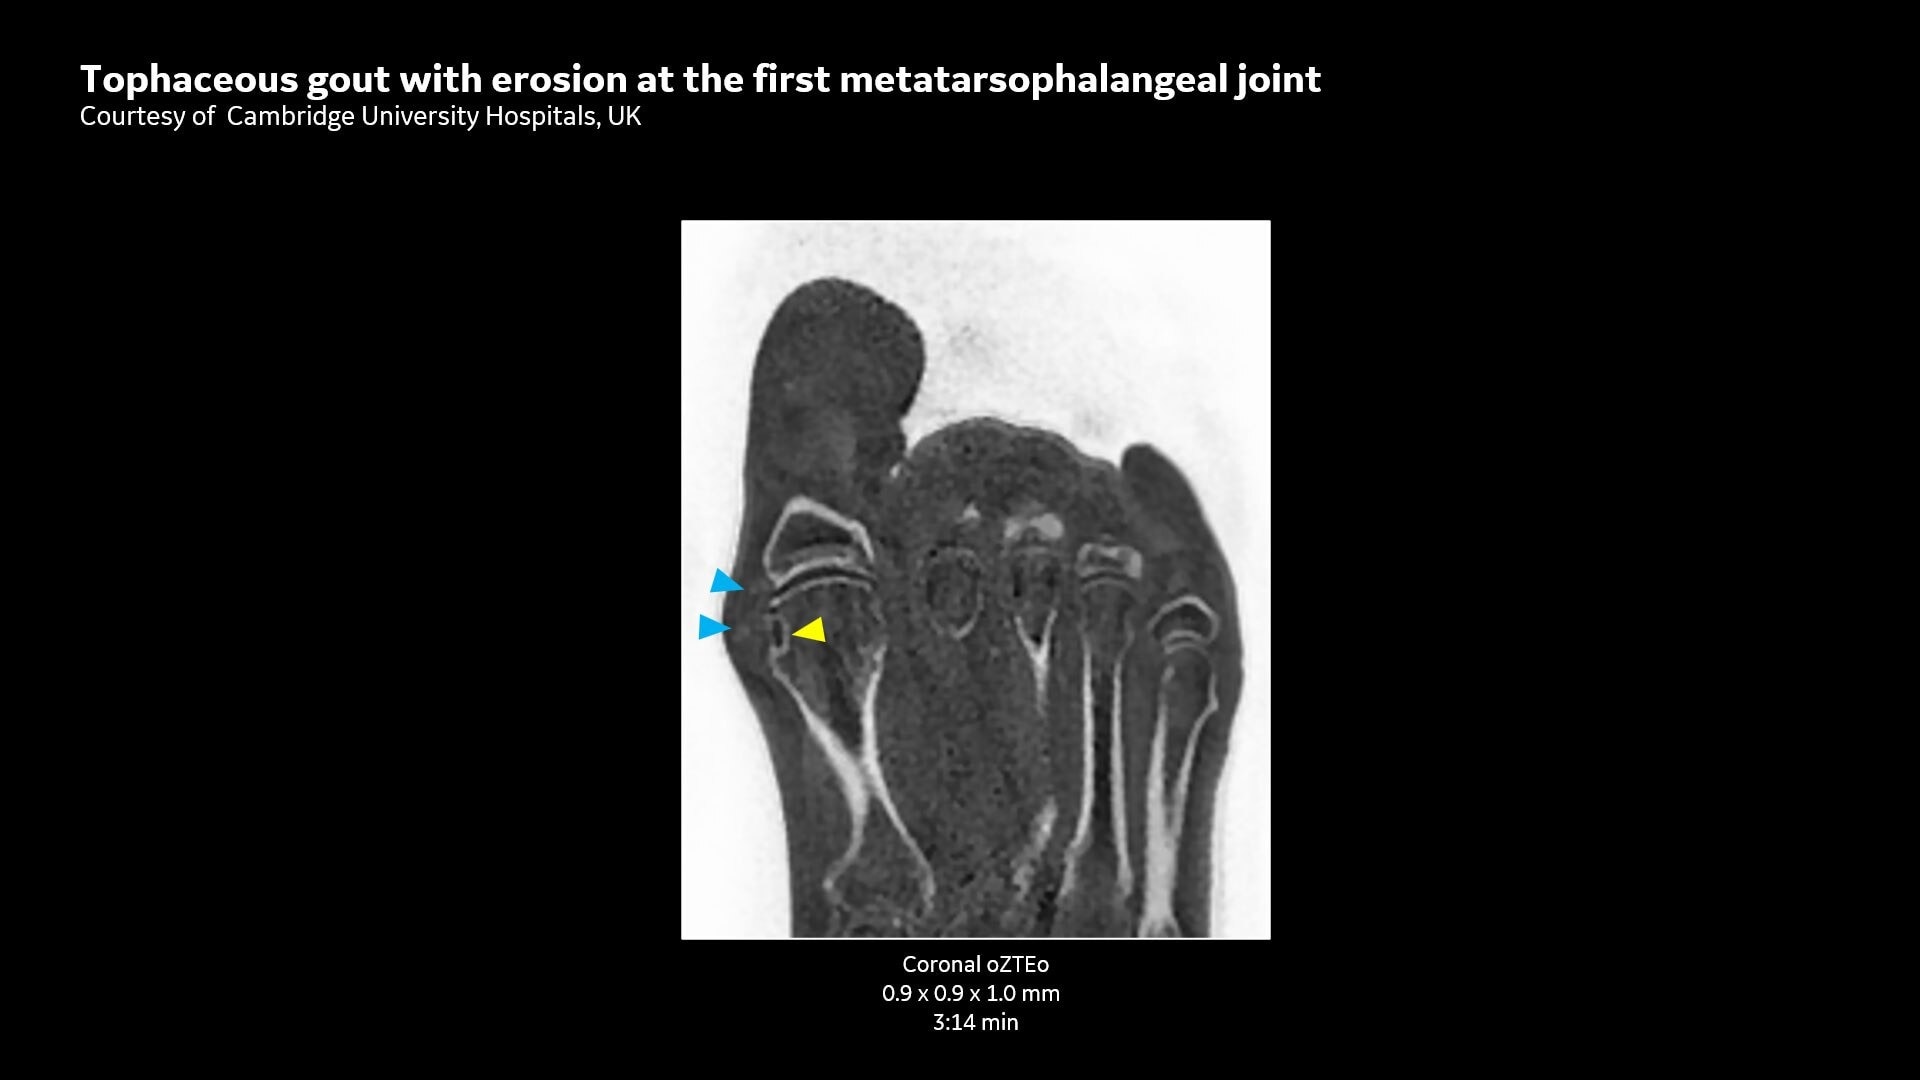

Provides cortical bone information co-registered with the soft tissue series

CT-like Image Contrast